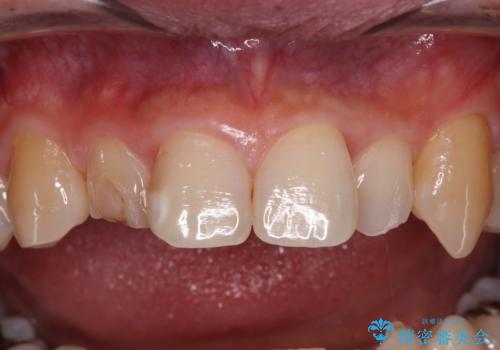

- 内側に倒れている前歯が擦れてしみるとのことで来院された患者様です。

削れていた部分は詰め物が入っていましたが、縁の部分がしみているようで、変色も目立っていたため、オールセラミッククラウンにて補綴治療を行うこととしました。

内側に倒れているため、下顎と強く干渉することが懸念されましたが、無理のない咬み合わせで、形態も左右対称に近い状態で仕上げることができました。